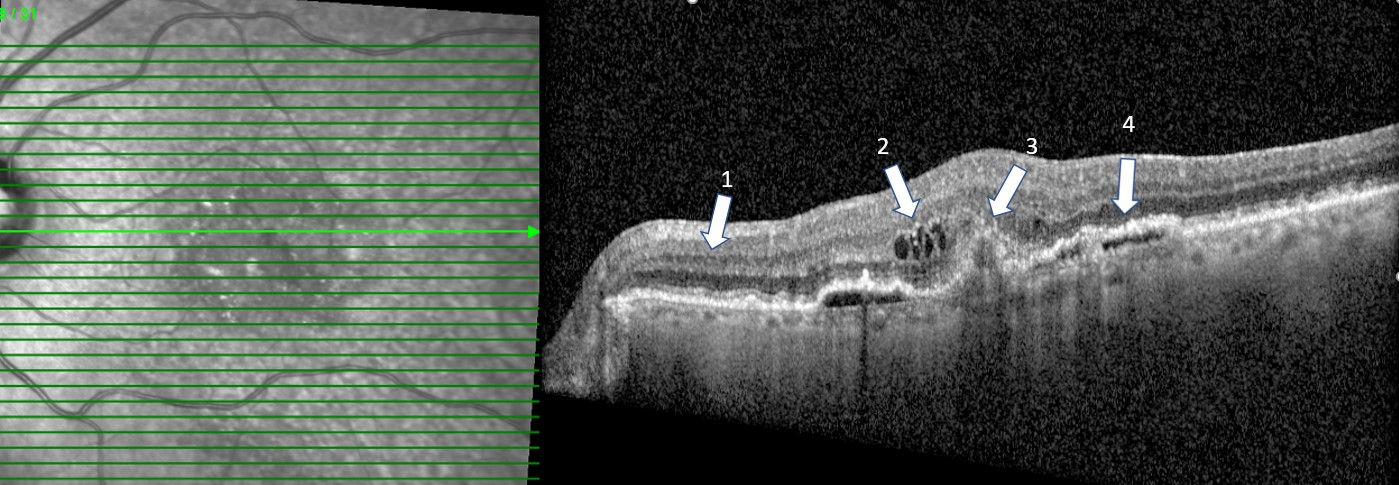

When we look at an OCT, we look at a cross section of the retina as shown in the left photo. The right photo is the cross section of the macula at the level of the bright green line shown on the left. (1) denotes a relatively normal retina. (2) represents retinal leakage (and thickening) within the retina or intraretinal edema (3) presents neovascularization or abnormal vessels below the retina that are the source of leakage, i.e. wet or exudative macular degeneration (ARMD) and (4) represents a different type of exudative macular degeneration with leakage under the retina. It is not important to understand the different layers of the retina and/or the degrees of leakage but to recognize that the OCT is the most critical test we do in order to diagnose, treat, and follow exudative macular degeneration.